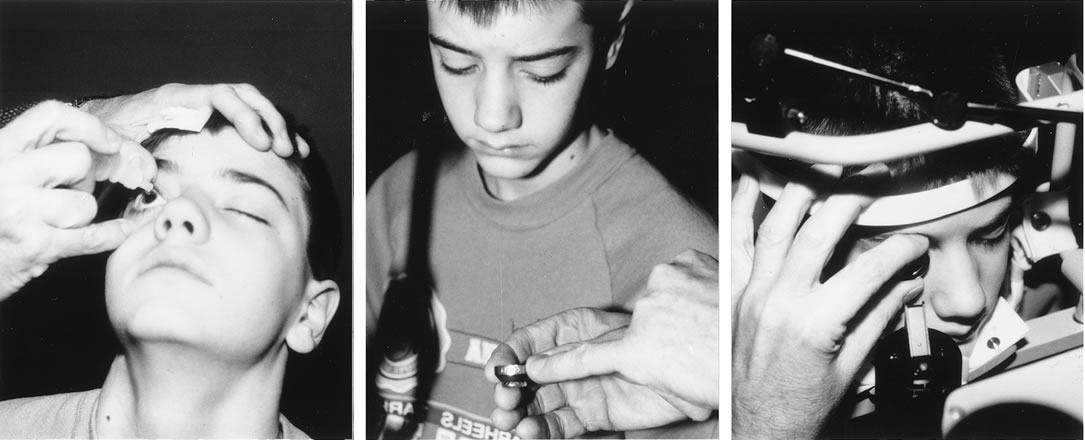

Until recently, application of laser technology for young or uncooperative children has been difficult because the instrumentation is bulky and difficult to transport. To some extent, these problems have been reduced with a reduction in the size of the laser. Use of the Nd:YAG laser to open the posterior lens capsule in young children has required that the patient be treated in a seated position. If the child is young or uncooperative, some surgeons have resorted to anesthetizing the child near the location of the Nd:YAG laser and have performed the laser treatment on the child while he or she is held in position for use of the laser delivery device. With this technique, there can be problems with positioning the eye, and if the child is treated at a location that is remote from the operating room, there may be difficulty in monitoring the child's anesthetic and providing emergency treatment if this would be required.

To overcome these difficulties, the Nd:YAG laser has been modified so that a posterior capsulotomy can be performed on a child in the supine position. The laser delivery systems now provide the surgeon with the ability to safely perform an Nd:YAG laser capsulotomy in children in the operating room with the assistance of sedation or, if necessary, general anesthesia (Fig. 4). In 1994, Atkinson and Hiles demonstrated the effectiveness of the Nd:YAG laser in children 3 months of age and older.29 The surgeon may elect to perform the Nd:YAG capsulotomy immediately after cataract surgery or at a later date, when the capsule has become tense or has begun to opacify.